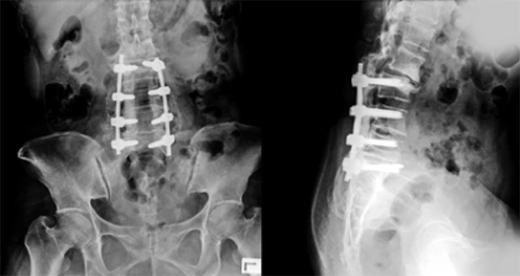

척추 유합술

복부를 최소한으로 절개하여 통증을 일으키는 손상된 뼈나 디스크를 제거하고 유합용 고정장치를 이용해 척추를 안정하게 고정시키는 수술입니다.